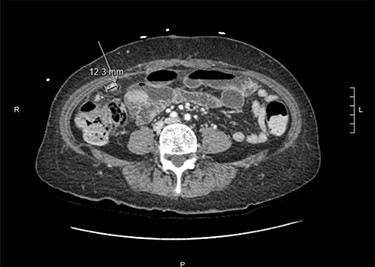

At that time, she presented to the ED with 2 weeks of abdominal pain. She was afebrile and hemodynamically stable. On examination, she had tenderness in the right upper quadrant (RUQ) and was noted to have diffuse cutaneous neurofibromas (Fig. 1). Her labs were unremarkable, except elevated alkaline phosphatase (137 U/l) and alanine transaminase (146 U/l). Computerized tomography of the abdomen and pelvis (CTAP) revealed a perihepatic cyst around the shunt catheter tip, appendiceal and peritoneal thickening, stranding along the right hemiabdomen and diffuse peritoneal nodularity with partial calcification (Fig. 2). Upon laparoscopic exploration and cyst unroofing, the patient was noted to have intra-abdominal inflammatory adhesions in the right hemiabdomen. Cerebrospinal fluid (CSF) cultures from the distal portion of shunt grew Staphylococcus epidermidis, and the patient was treated with intravenous antibiotics.

Computerized tomography of the abdomen and pelvis demonstrating appendiceal and peritoneal thickening.